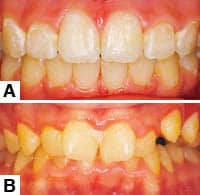

Patients seek orthodontic treatment mostly for esthetics issues even if they have functional occlusal problems. The orthodontist and parent or patient invests time, material, expense, and expertise to achieve beautiful smiles. When the day for appliance removal is finally reached, everyone from patients, families, and the treating orthodontist and staff are excited. However, the euphoria is short-lived when noticeable decalcification, in the form of white/brown spots resulting from poor oral hygiene during treatment, ruin the esthetic value of the case (Figure 1A).

| Figure 1: (A) Decalcification and gingival infection post-treatment. (B) An example of poor oral hygiene pretreatment. This type of patient should not be treated until the gingival problems are rectified. |

At the initial exam, the doctor should perform a complete periodontal exam that assesses the health of the periodontium and the patient’s oral hygiene. If the oral exam shows plaque accumulation and gingival bleeding, then this patient should not be considered for orthodontic treatment until the gingival tissues are completely healthy (Figure 1B).